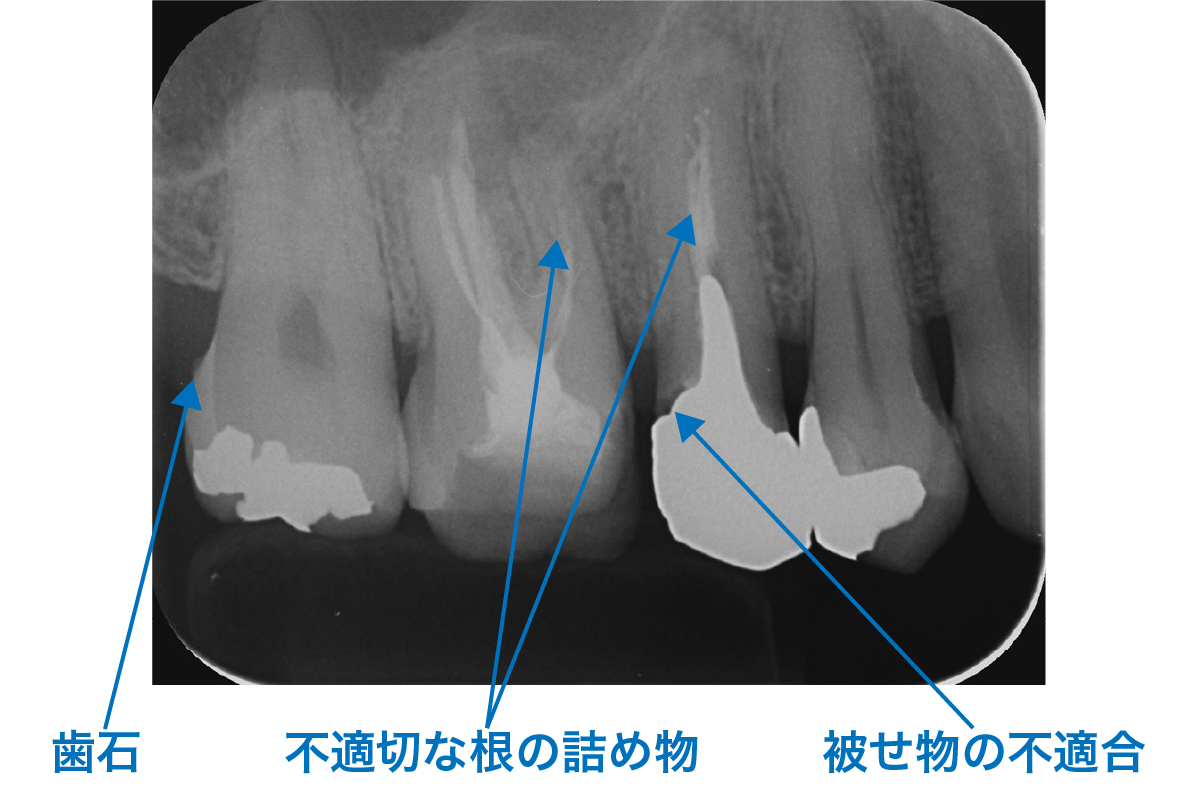

X線写真検査(レントゲン)

歯の周囲の骨の状態の観察、歯石の付着状態の観察はもちろん、虫歯や不適合のかぶせものなど、歯周病に悪影響を与える要因の発見にも有効です。